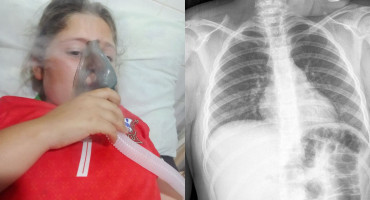

Una conocida vendedora de la Feria Municipal de Encarnación, doña Aurora González, de 70 años, atraviesa un delicado momento de salud a raíz de problemas musculares que le impiden continuar con su labor diaria.

Una madre encarnacena vive horas de angustia tras el grave accidente que sufrió su hijo de 17 años el pasado viernes 28 de noviembre, sobre la ruta PY06, a pasos del acceso al Hospital General de Itapúa.

La comunidad de Cambyretá se encuentra movilizada ante la difícil situación que enfrenta una familia local, afectada por un grave accidente de tránsito ocurrido el pasado sábado.

En una humilde vivienda del barrio Ita Paso, vive Doña Felicita Cáceres, una mujer de 56 años que hoy enfrenta una de las batallas más duras de su vida: la de no quedar completamente ciega.